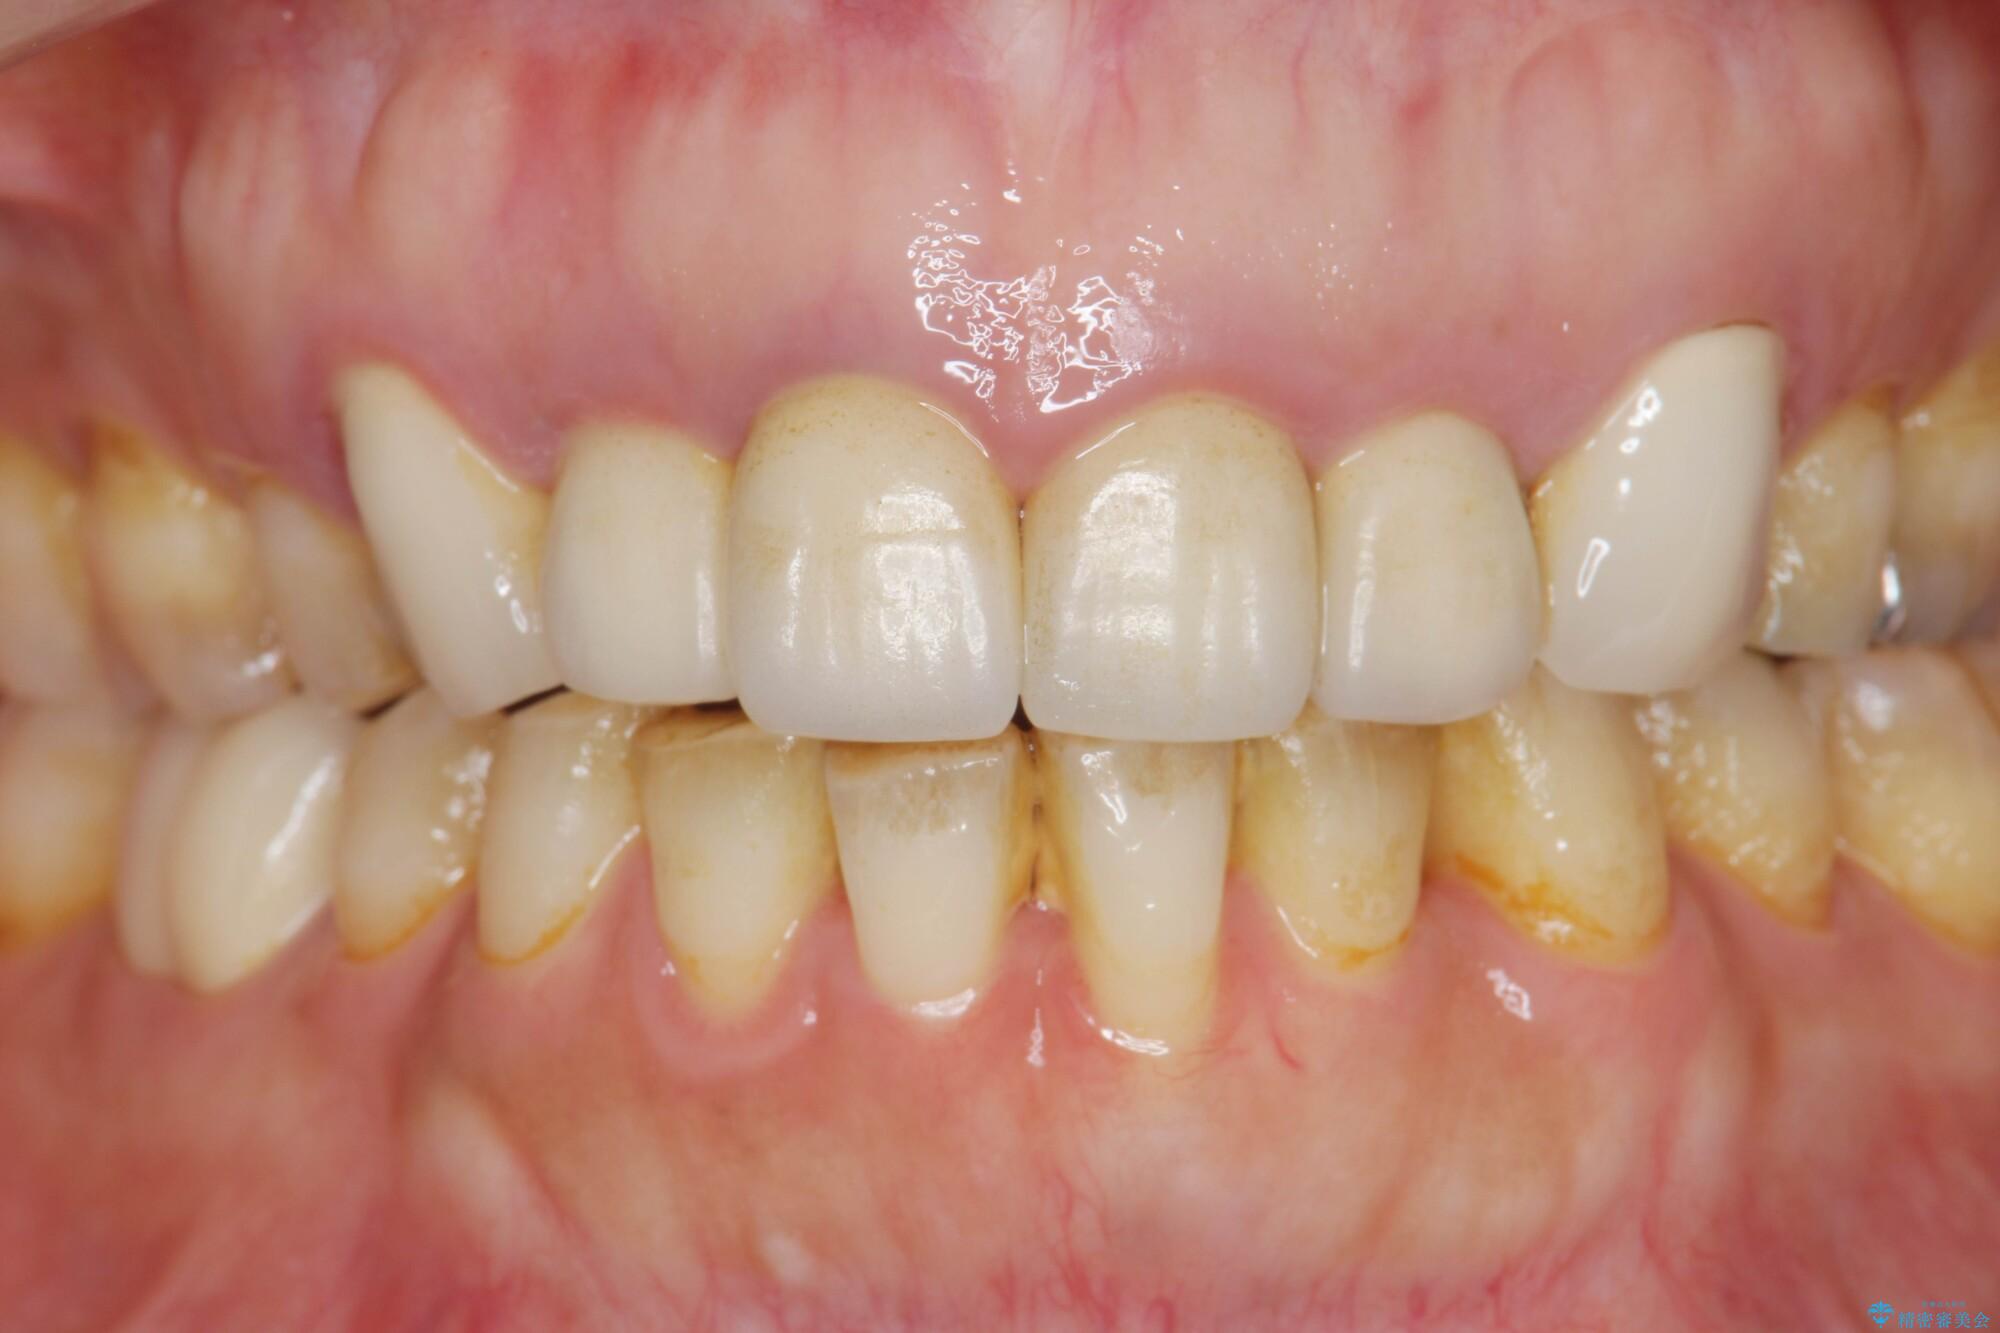

以前に他院で行ったセラミック治療後に、慢性的に歯ぐきからの出血や疼き、違和感がありご相談にいらっしゃった患者様です。

治療計画

装着されていたセラミックを除去したところ、歯ぐきの奥深くまで歯牙は削られ、歯ぐきの炎症・出血が著しくみられる状態でした。